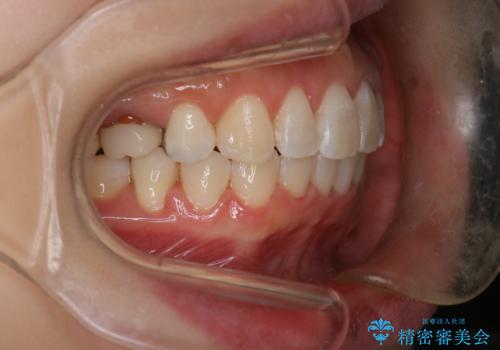

抜歯を行い、前歯のがたつき、前歯の出ているところを改善できました。

患者様の満足感も高く治療を終えられました。